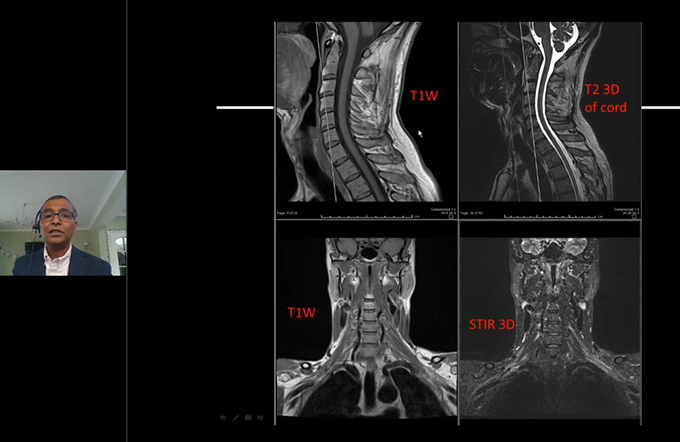

Advance Quantitative Imaging of the Spine |

Dr. James F Griffith |